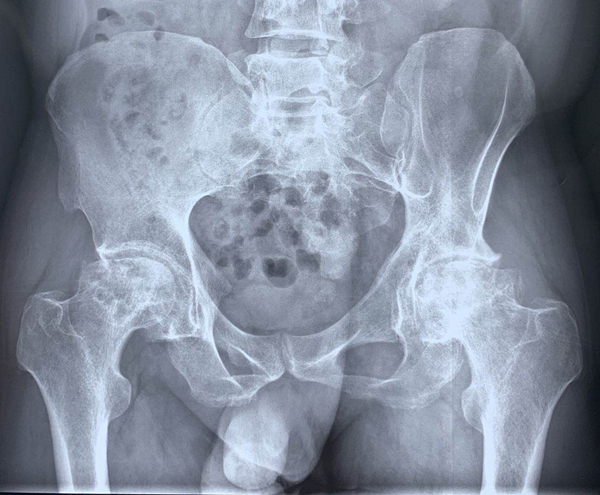

圖一

李寬新主任接診后詳細(xì)詢(xún)問(wèn)病史、體格檢查(圖一),結(jié)合患者術(shù)前骨盆平片,骨盆CT(圖二、三)平掃三維重建,診斷為:“雙側(cè)股骨頭壞死繼發(fā)終末期骨關(guān)節(jié)炎(Ficat IV期)”。為實(shí)行快速康復(fù),精準(zhǔn)解剖重建髖關(guān)節(jié),提出應(yīng)用微創(chuàng)OCM入路聯(lián)合Harris窩技術(shù),實(shí)現(xiàn)微創(chuàng)和精準(zhǔn)全髖關(guān)節(jié)置換的治療方案。